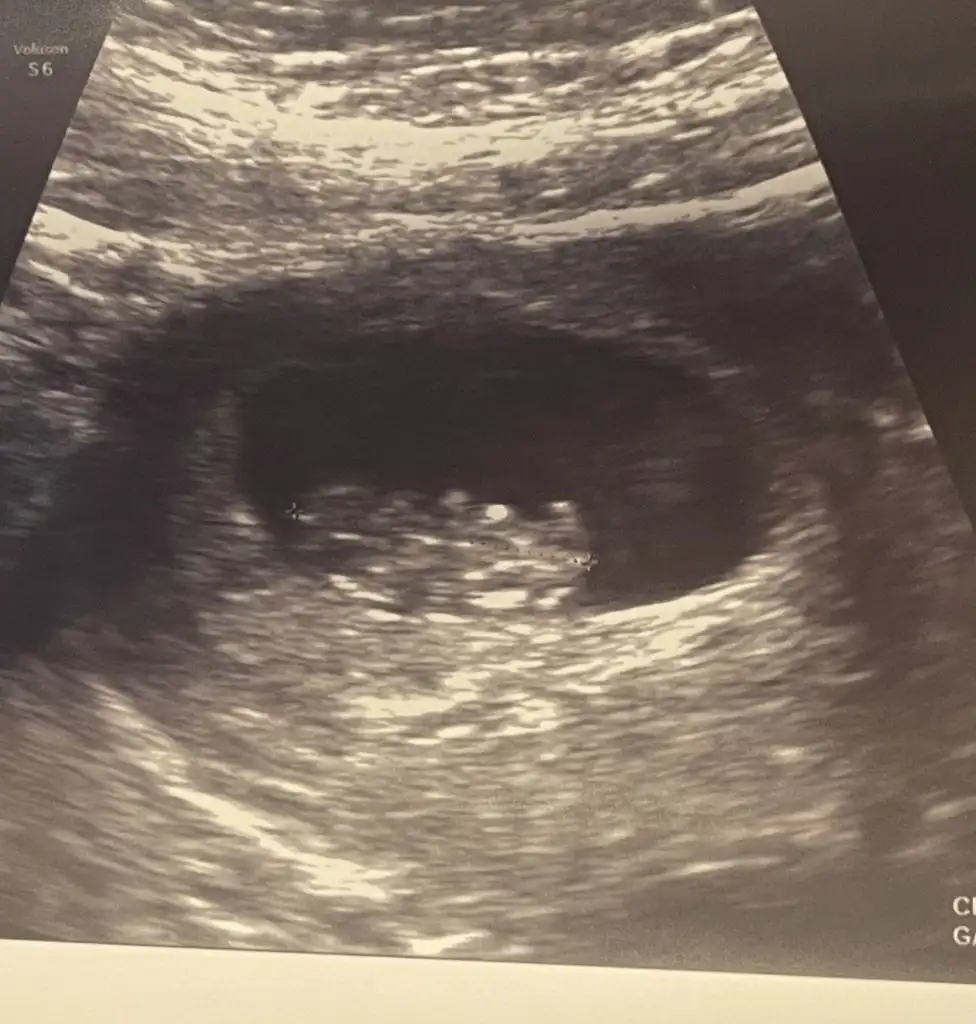

Merhaba canım çok şükür bugün bir kez daha rahat nefes alarak oh çektim bebeğim benimle ve büyüyor Rabbim sağlıkla kucağımıza almak nasip olsun inşallah. Tahmin varmı acaba iki kese vardı biri kaybolmaya başlamış tek gebelik devem ediyor. Ultrasonda hareketlerini yakaladık. 3 gün önden gidiyormuş. Maşallah rabbim hepimizin evlatlarının güzel haberlerini almak nasip olsun.